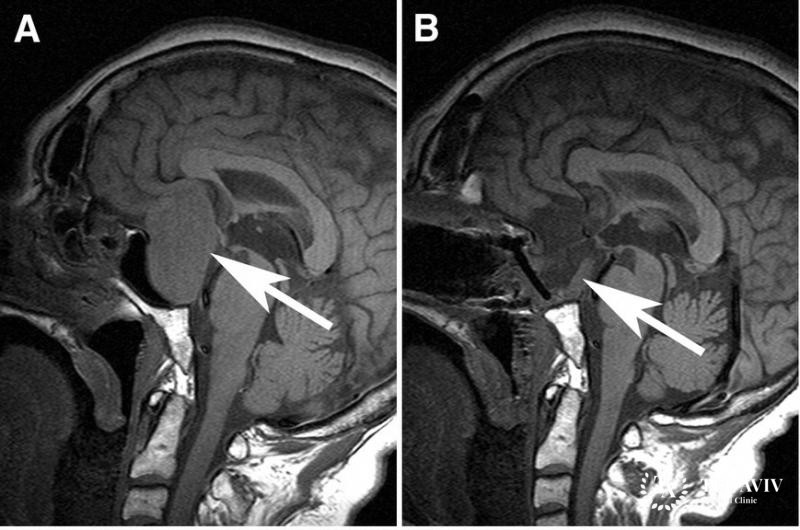

Аденомы гипофиза – новообразования, имеющие доброкачественный характер. Место их дислокации – аденогипофиз, передняя доля.

Методики лечения различаются, в зависимости от размерности новообразования. Если они небольшие, никак себя не проявляют, достаточно регулярного осмотра, контролирующих состояние анализов. Врач назначает консервативное лечение при психологических нарушениях, неврологической патологии, эндокринопатии.

При наличии осложнений, крупных образований, рекомендует операция. Существует несколько подходов к хирургическому вмешательству: